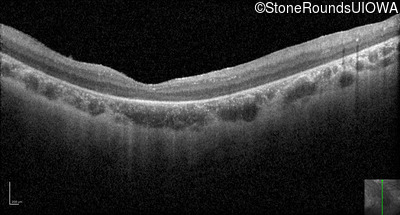

Optical Coherence Tomography - Left - 10/350 sc

Exemplar / OCT Stack